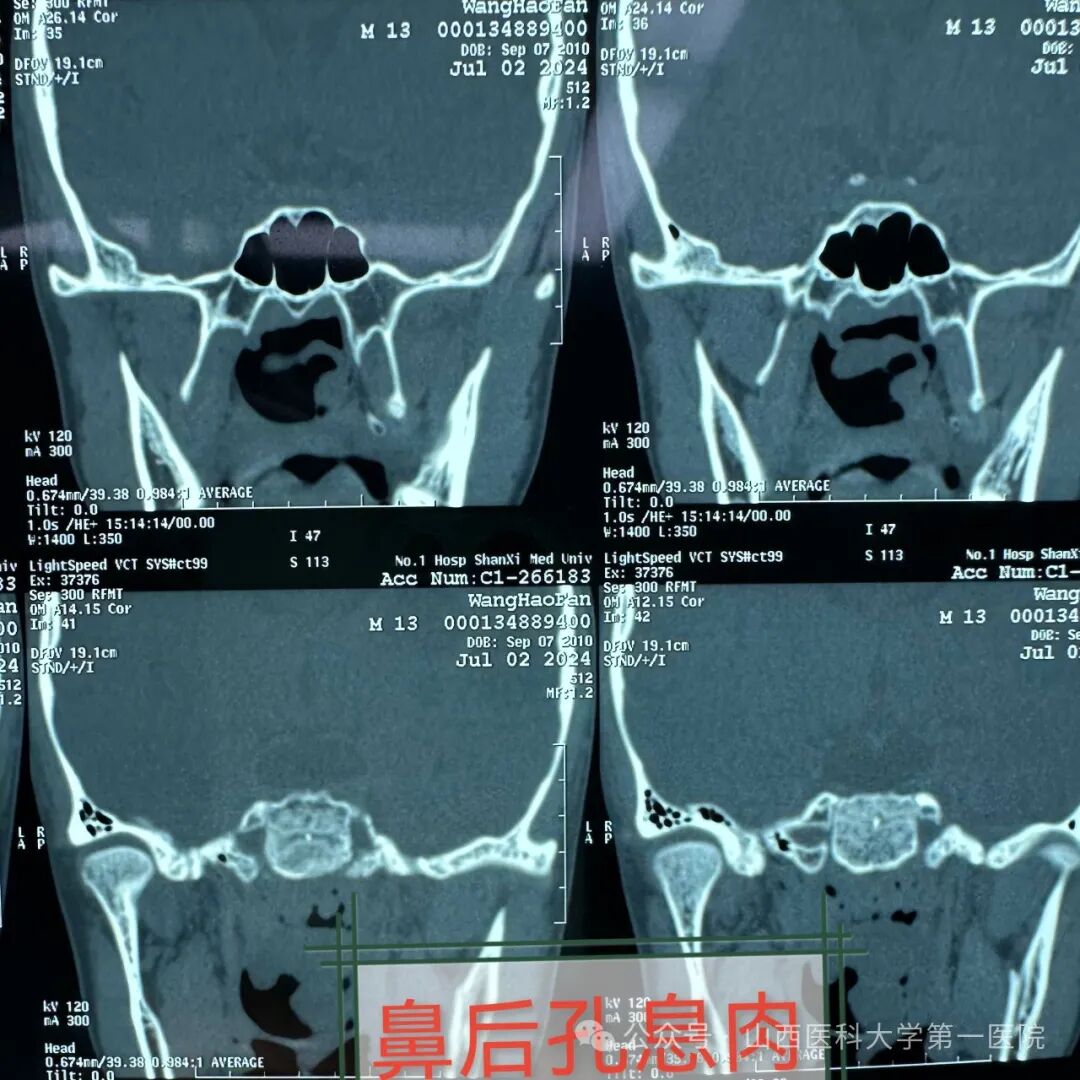

通过检查发现单侧鼻腔多量淡红色荔枝肉状肿物完全堵塞鼻孔,鼻窦轴位与冠状位CT示鼻腔及上颌窦充满低密度影,鼻腔鼻窦占位性病变,初步考虑为鼻腔鼻窦息肉,而鼻腔鼻窦息肉是一种良性病变,易复发、不易恶变,治疗关键是手术完整彻底切除病变。